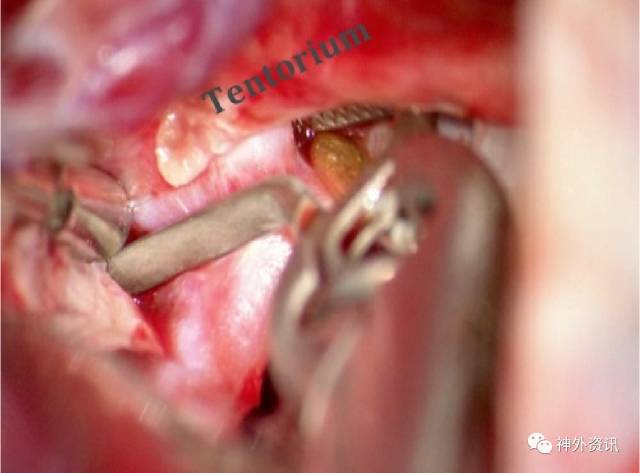

图26:PCoA动脉瘤偶尔突到小脑幕缘下。完全暴露瘤颈可能需要在小脑幕切一个小切口。有些动脉瘤囊甚至同时突入在小脑幕上下的脑叶中。